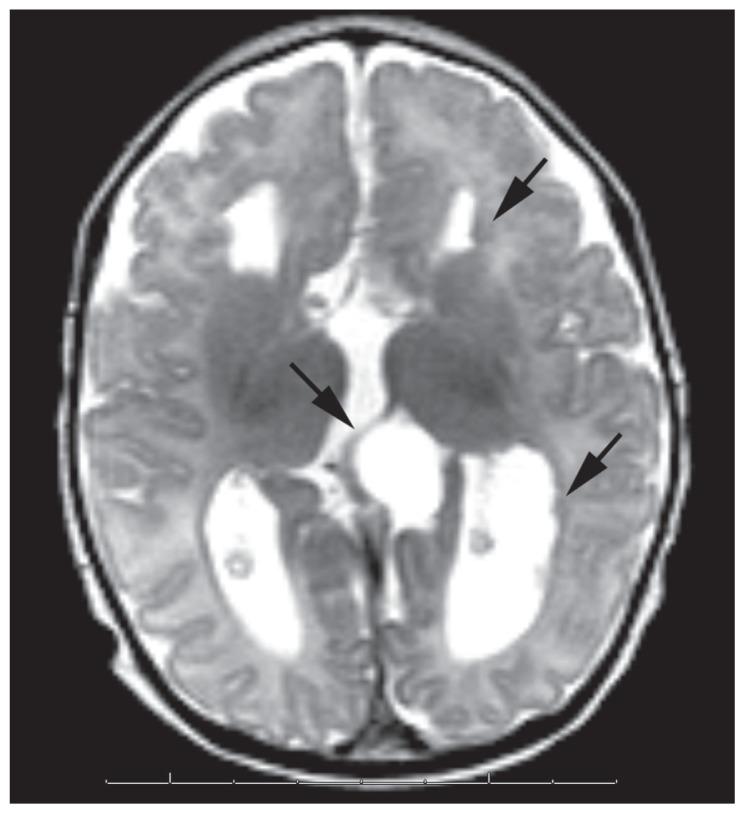

Aicardi syndrome (AS) is an X-linked inherited disorder characterized by infantile spasms, chorioretinal lacunae, and agenesis or hypogenesis of the corpus callosum. The syndrome is more frequently seen in females but is observed in XXY male patients. Central nervous system, ocular, and costovertebral malformations may also seen in AS. Eye findings are of a considerable diagnostic importance; the chorioretinal lacunae are pathognomonic for AS and are generally bilateral. The outcome of the disease is generally severe, with a high mortality rate and poor developmental outcome. It is not clear which characteristics of the syndrome are related to a good prognosis in terms of psychomotor development, epileptic seizures, and survival. The purpose of this report was to demonstrate the spectrum of the clinical findings and the course of AS in two Turkish patients with different ocular and cranial MRI findings.

艾卡迪综合征(AS)是一种X连锁遗传性疾病,其特征为婴儿痉挛、脉络膜视网膜缺损以及胼胝体发育不全或发育不良。该综合征在女性中更为常见,但在XXY男性患者中也有发现。中枢神经系统、眼部和肋椎畸形在AS中也可能出现。眼部表现具有相当重要的诊断意义;脉络膜视网膜缺损是AS的特征性表现,通常为双侧性。该病的预后通常较差,死亡率高且发育结局不佳。目前尚不清楚该综合征的哪些特征与精神运动发育、癫痫发作和生存方面的良好预后相关。本报告的目的是展示两名土耳其患者的临床发现谱以及AS的病程,这两名患者具有不同的眼部和头颅MRI表现。